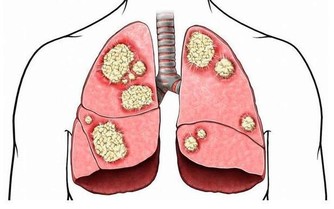

膝關節構造是由骨頭,即股骨、脛骨、髕骨,關節軟骨及軟組織,如關節滑囊、關節液及周圍肌肉韌帶構成,關節軟骨是否正常,以及關節液是否充足,都仰賴關節負重活動,如走、跑、跳等,幫助關節靈活順暢。

由於藥物及復健皆難以直接改善軟組織及關節面軟骨問題,因此增生療法近年來成為治療的一環,主要在於鎖定軟組織病灶及關節面軟骨來施打藥劑,如高濃度葡萄糖、維生素B12、自體血小板生長因子等,幫助軟骨修復及軟組織回復強韌,以提升生理結構完整性與關節穩定度。